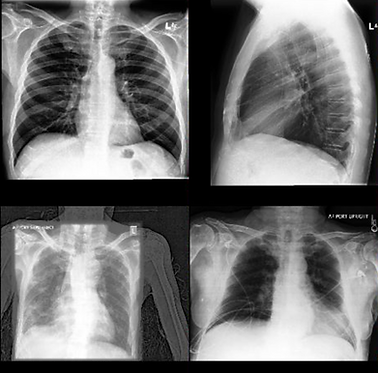

1. Chest X-Ray

Elevate routine chest imaging into a comprehensive screening tool. MedCognetics' AI-powered chest X-ray platform supports detection and screening of lung diseases, delivering faster triage, more consistent reporting, and improved outcomes across diverse patient populations.